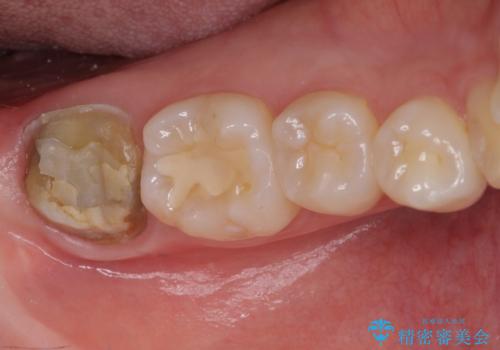

- 奥歯のかぶせものが頻繁に脱離することを気にされて来院された患者様です。

歯の高さが低く、かぶせものを安定して維持させることができないため、歯冠長延長術により歯の高さを増大させた上で、オールセラミッククラウンにて補綴することとしました。

クラウンが外れている期間も長く、虫歯が進行していたため、根管治療も行うこととしました。